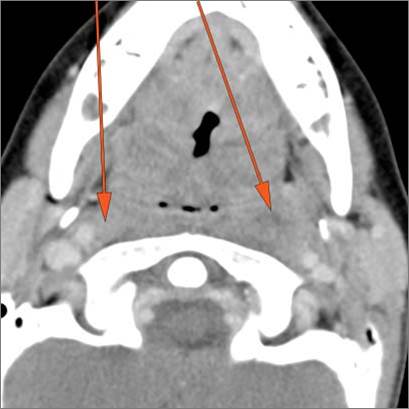

9 month old male presenting to the emergency room with poor feeding, fever, respiratory distress and possible retropharyngeal abscess or suppurative retropharyngeal adenitis.Exam

There is excessive enhancement or thickening of the mucosa or hypertrophy of the palatine or lingual tonsillar tissue or the lymphoid tissue along the glossotonsillar sulci and posterior pharyngeal wall. |

Yes | NA |

There is reactive retropharyngeal lymphadenopathy. |

There is suppurative retropharyngeal lymphadenopathy. |

Pharyngitis with suppurative retropharyngeal adenitis.